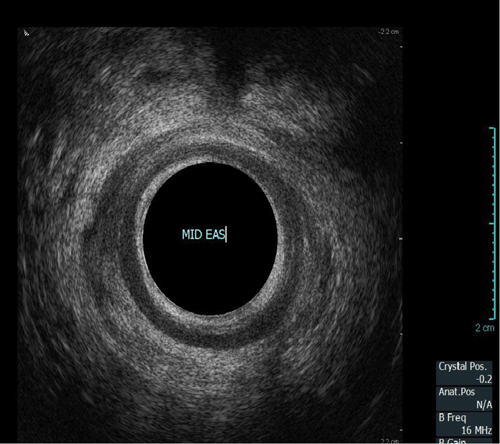

This procedure is indicated for assessment of the anal sphincter in patients with incontinence. This allows evaluation of the internal and external anal sphincters (sphincter thickness, length and scarring). It is pertinent to obtain history of obstetric trauma as well as any surgeries / intervention to aid assessment.

As with the proctogram technique, the procedure is explained in detail and consent obtained prior, and the presence of a chaperone makes the patient more comfortable. Digital rectal examination is performed as a reference to assess anal tone. Still images as well as cine of the ultrasound are taken to assess the sphincter complex (Figure 3).

Figure 3a: (Top, middle and bottom) Normal endoanal ultrasound.